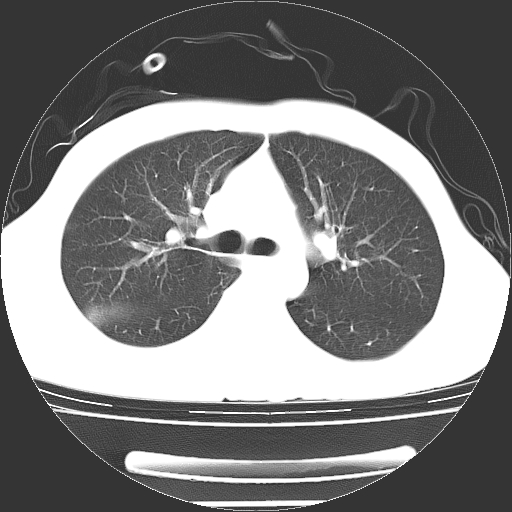

以下是引用zjzjr在2008-4-29 14:11:00的发言:[br]支持右侧胸腔包裹性积血。闭式引流管是不是插的太深了?胸腔引流,引流管快进入纵隔了.